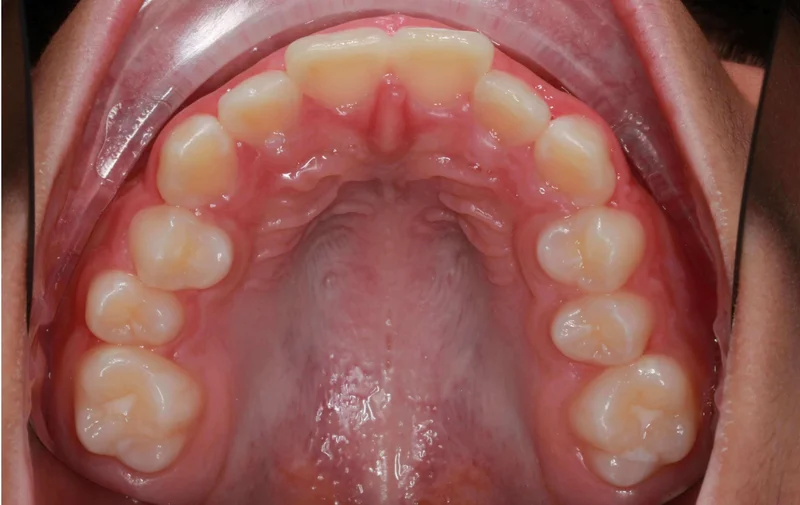

Upper Occlusal View

Upper Occlusal View - Before Treatment

Before